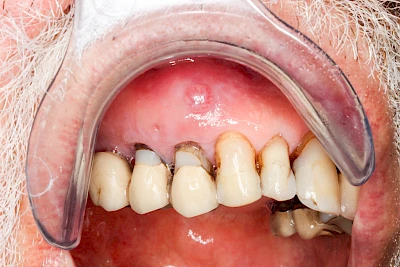

Bei einer Fistel hat sich meist eine Entzündung (manchmal auch Erreger selbst) z. B. aufgrund von Karies oder aufgrund eines Unfalls über den Zahnnerv und die Wurzelspitze (Apex) in den umliegenden Knochen ausgebreitet (apikale Parodontitis) und schnell einen Weg durch den umgebenden Knochen und die aufliegende Schleimhaut in die Mundhöhle gebahnt.

Fisteln sind in der Regel nicht schmerzhaft und fallen häufig als kleine Öffnung weiter entfernt vom Zahnfleisch nahe der Umschlagfalte auf. Aus der Fistelöffnung entleert sich spontan gelbliches Sekret (Eiter) oder es lässt sich mit dem Finger ausstreichen. Manchmal beschreiben die betroffenen Menschen immer wieder einen komischen Geschmack im Mund.

Im fortgeschrittenen Stadium kann die Schleimhaut sich weiter zurückgezogen haben und die Wurzelspitze sichtbar sein. In der Regel treten bei Fisteln keine Schwellungen auf, weil sich die Entzündung nicht im Gewebe ausbreitet.